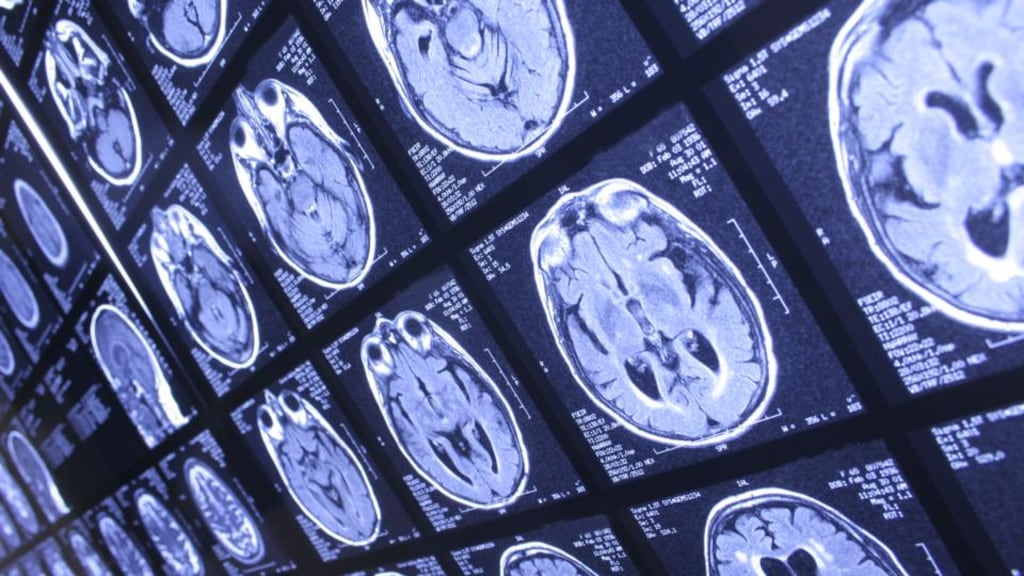

The software error in the National Integrated Medical Imaging System (Nimis) meant potentially thousands of patient records from MRIs, X-rays, CT scans and ultrasounds were recorded incorrectly and may have led to patients’ undergoing unnecessary treatment. Change Healthcare, which is based in Canada, said it is “working hard to understand exactly what happened in this case”.

In the past six years 23,302,968 records have been created on Nimis, for 6,109,043 people. Of those records, 21,131 were affected by the “<” error. The HSE is working to establish what effect the error had on patient outcomes in 2,500 of the affected scans. It says it will widen its own investigation to cover more affected scans if it turns out that large numbers of patients were affected.